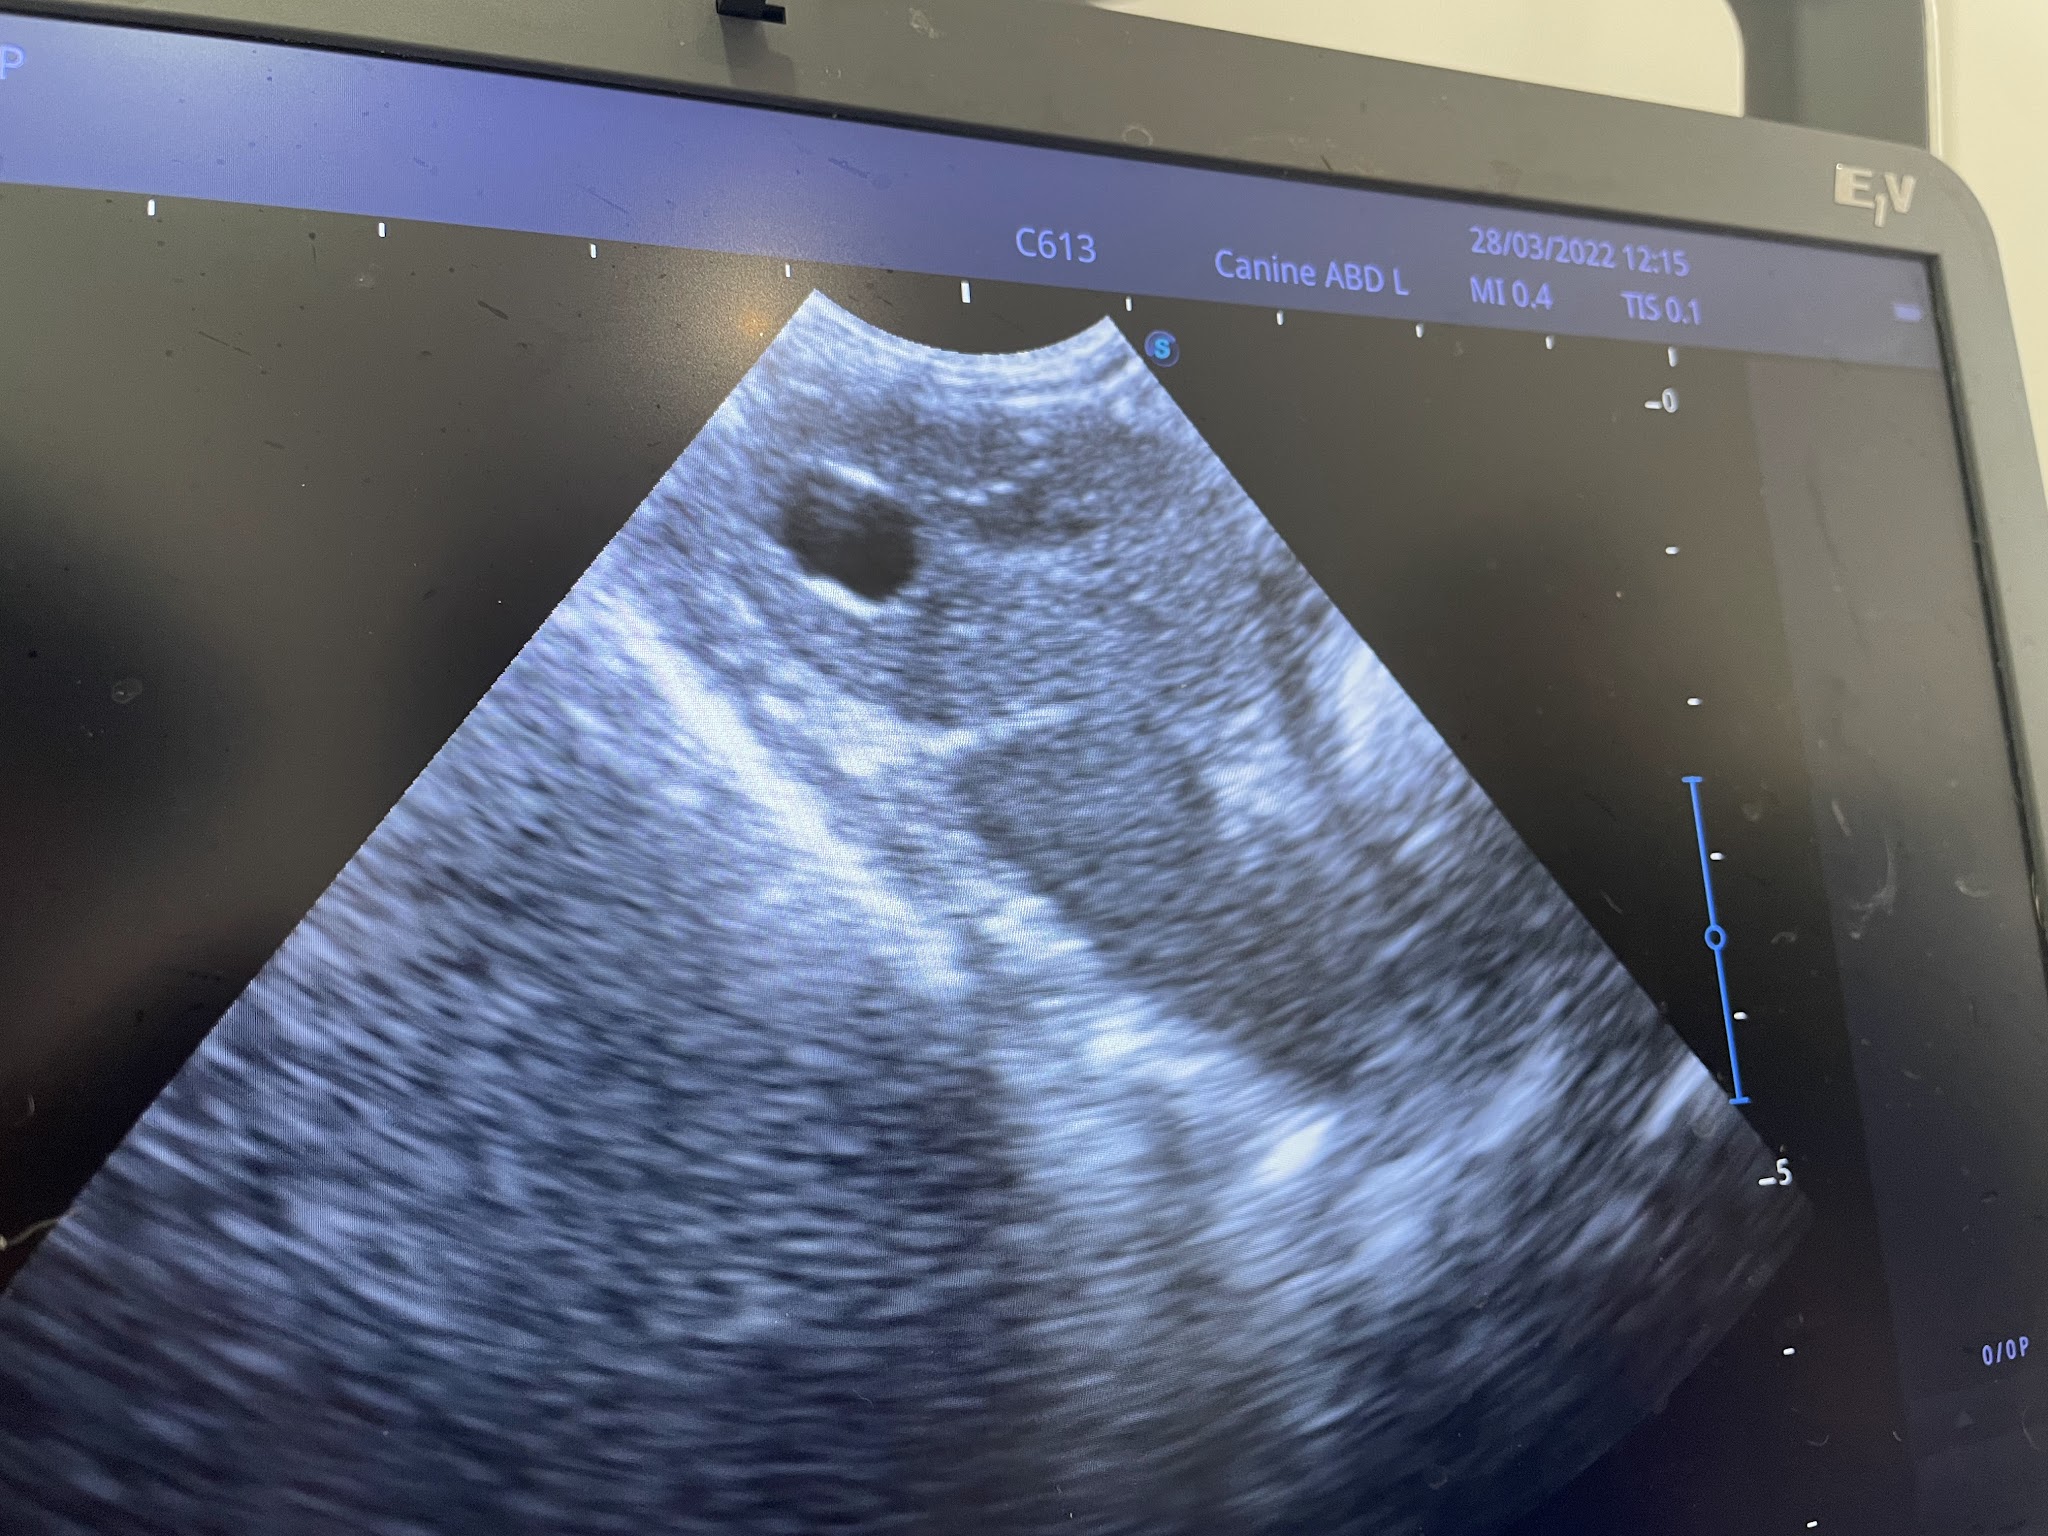

Facilidades Veterinarias Avanzadas

Equipado con facilidades veterinarias avanzadas, el hospital ofrece atención veterinaria integral, con un enfoque en procedimientos quirúrgicos.